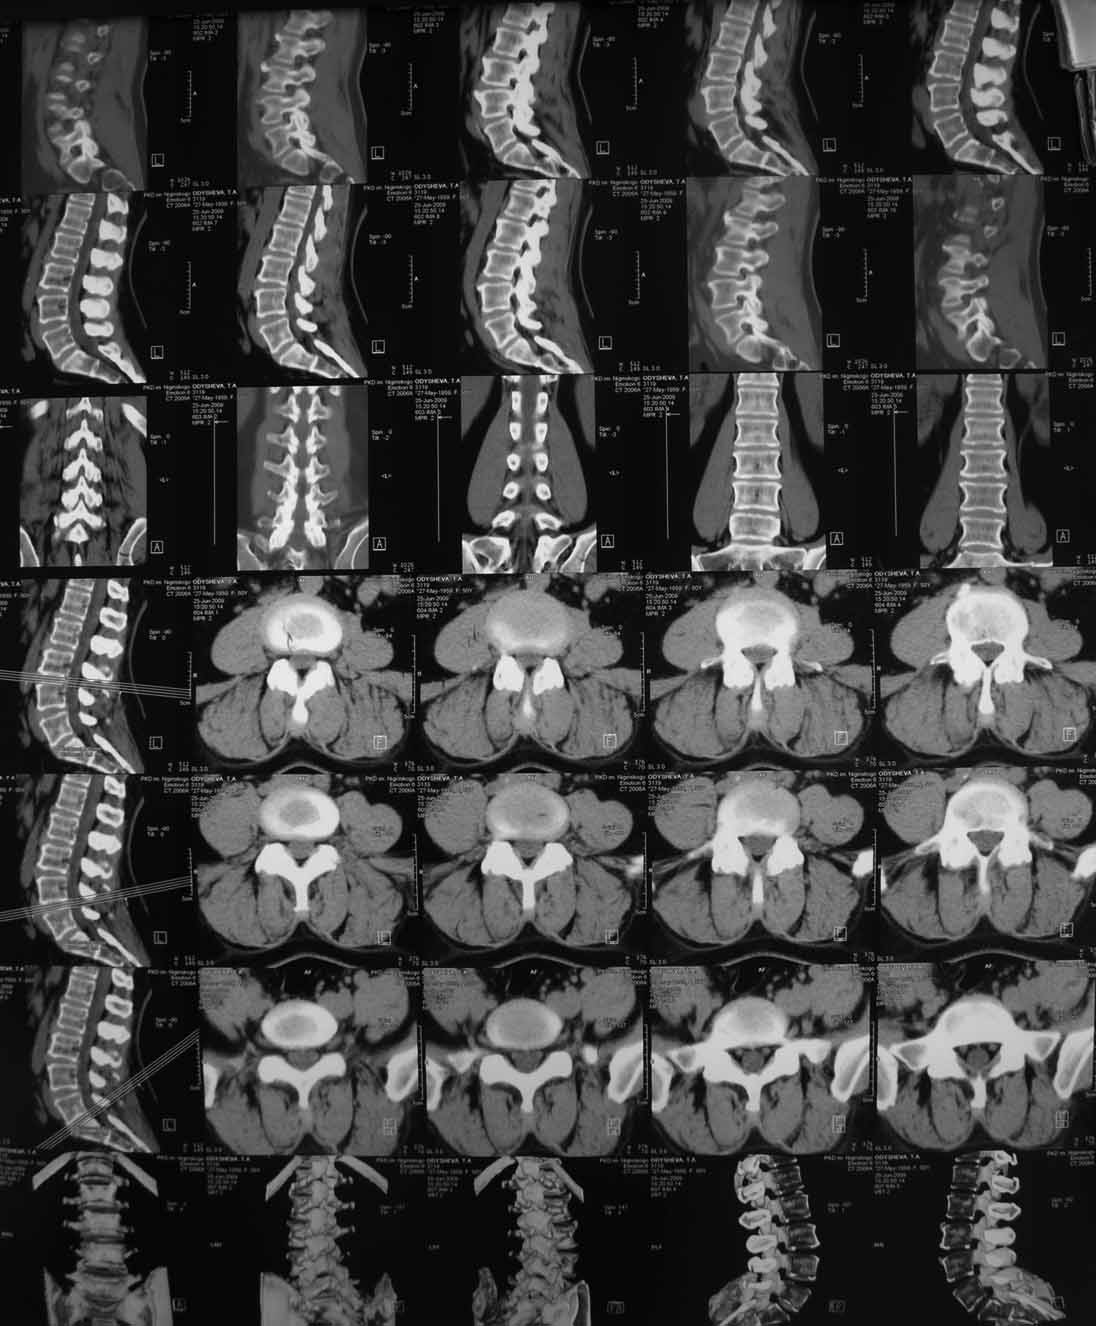

В 2009г установлен диагноз - сакроилеит справа.На представленных КТ имеется гипертрофия заднего отдела правой подвздошной кости с образованием контакта с задней поверхностью крестца.В январе 2011 года выполнена попытка удаления гипертрофированного участка подвздошной кости. удаленные участки кости исследованы гистологически - губчатая кость с элементами гиалинового хряща. После операции положительного эффекта не получено. На контрольной КТ от 04.2011 обнаружено что, желаемого результата операции не получено(интересующий участок удален частично), при этом имеется расслоение заднего отдела правой подвздошной кости.

На первичных КТ от 19-12-2009 определяется частичное анкилозирование правого крестцово-подвздошного сочленения, а на последних, от 11-04-2011 протяженность анкилозированной зоны значительно больше - сакроилеит прогрессирует, (с левой стороны вроде тоже признаки сакроилеита появились - не очень понятно из-за качества снимка). Значимых дуральных и радикулярных конфликтов действительно нет. "расслоение кости" - рентгенологически выглядит как травматический перелом подвздошной кости. Что делать? - наверное, искать серонегативные спондилоартропатии у ревматолога.